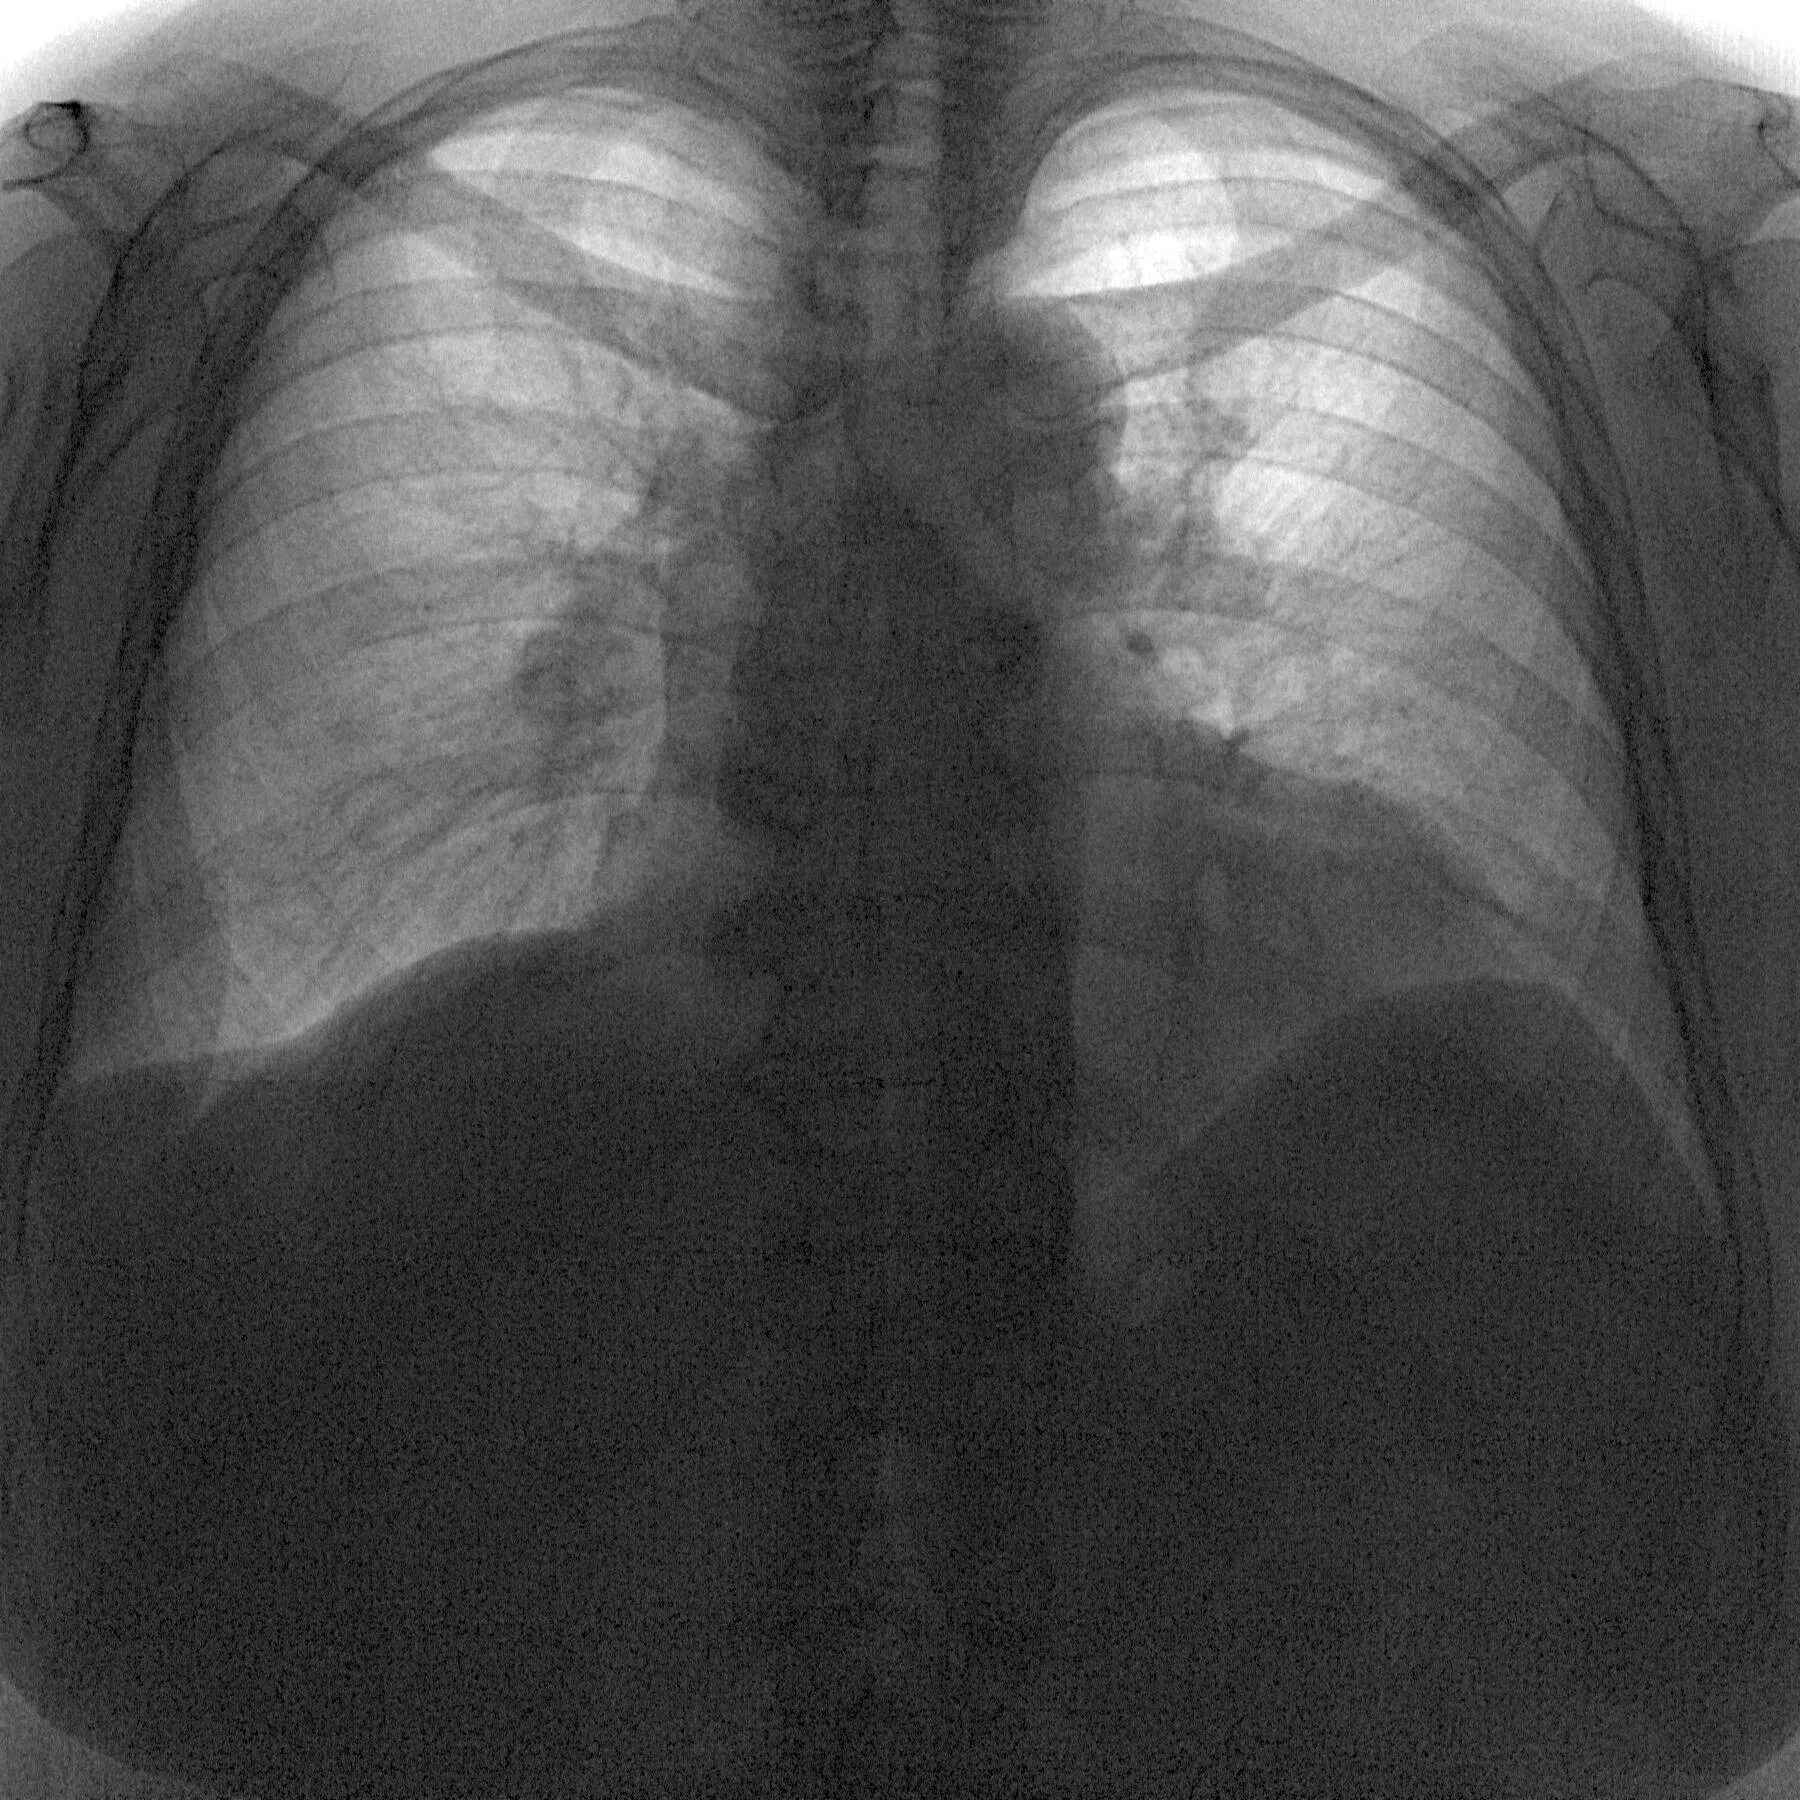

Флюорография видно ли курящего электронную сигарету